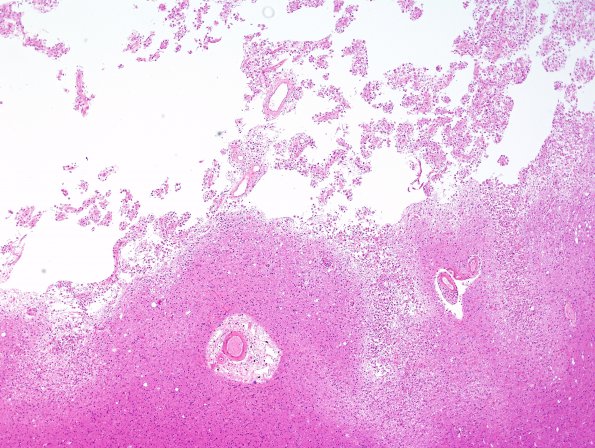

Washington University Experience | VASCULAR | Small Vessel Disease | 4A3 Hemorrhage, infarcts, arteriolosclerosis, hypertension (Case 4) H&E N15 2

4A3,4 At the margins of the infarct numerous arteriosclerotic vessels are prominent. (H&E)